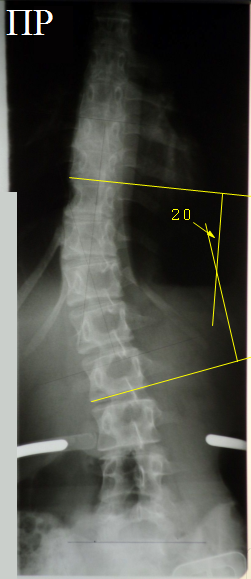

Слева

показан фрагмент прямой рентгенограммы позвоночника с нижними поясничными

позвонками, не имеющими ротации. Остистые отростки лежат на средней линии,

справа и слева от неё симметрично лежат тени ножек дуг позвонков. Справа

показан фрагмент прямой рентгенограммы позвоночника, на котором отображена

вершина сколиотической дуги в области 12 грудного и 1,2 поясничных позвонков.

Угол дуги большой (20°), выражены признаки ротации позвонков в области

вершины дуги: тени остистых отростков лежат не на середней линии тел позвонков,

тени правой и левой ножек дуг лежат не на одинаковом расстоянии от средней

линии тел позвонков. Зеленые стрелки – тени остистых отростков, желтые – тени

ножек дуг.